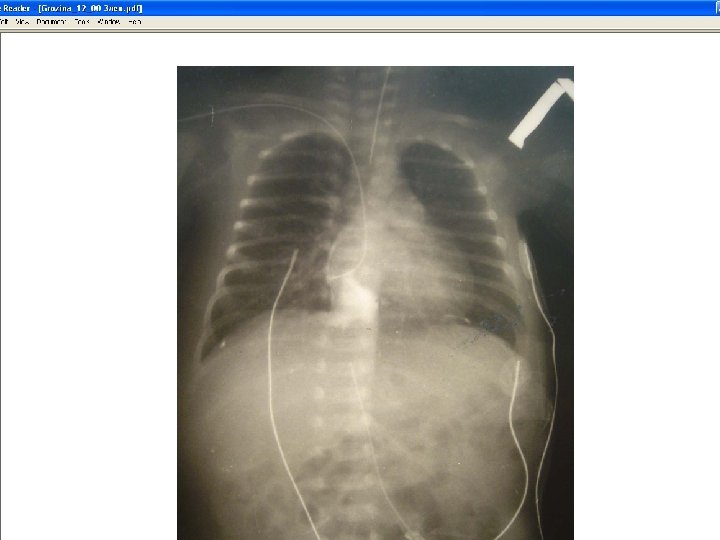

Peripherally Inserted Central Catheter (PICC) • Length ranges from 40 to 65 cm. • Basilic vein is the preferred site for insertion; cephalic vein can be used. • Placement is confirmed by chest x-ray examination. • No information is available on optimal dwell time. • Teach clients to perform normal ADLs, avoiding excessive physical activity.

Nontunneled Percutaneous Central Catheter • Inserted through subclavian vein in the upper chest or jugular veins in the neck • Usually 15 to 20 cm long • Tip resides in the superior vena cava • Placement confirmed by chest x-ray examination • No recommendations for optimal dwell time